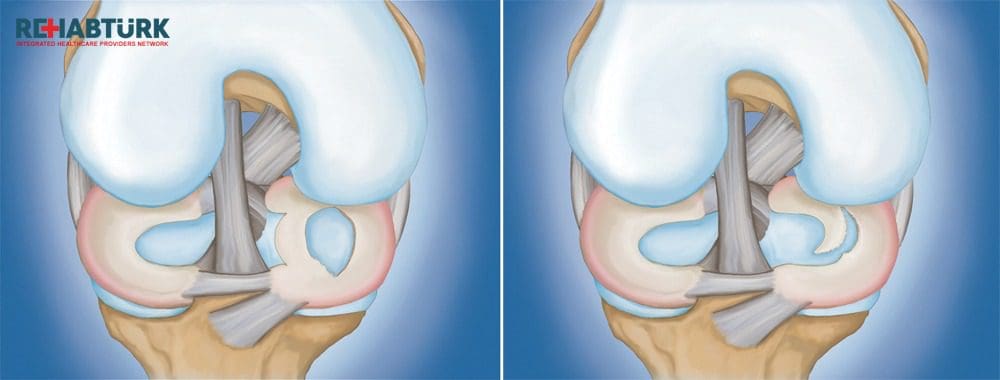

أطباء العظمية والمفاصل

81 listings